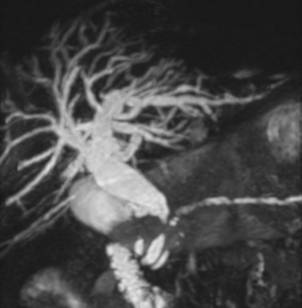

По клинической симптоматике пациенты были разделены на две группы: ,40%) – с синдромом болевой механической желтухи,,60%) – с синдромом безболевой механической желтухи. Причинами обтурационной желтухи у ,91%) пациентов явились: желчнокаменная болезнь, холедохолитиаз (Рис. 1), у,73%) – заболевания (опухолевые и неопухолевые) желчных протоков, прочие болезни панкреатобилиарной зоны, вызывающие внешнюю компрессию желчных протоков (Рис. 2), составили 30,36% (75 больных). (табл. 1).

Рис. 1 МРХПГ. Конкремент в общем печеночном протоке.